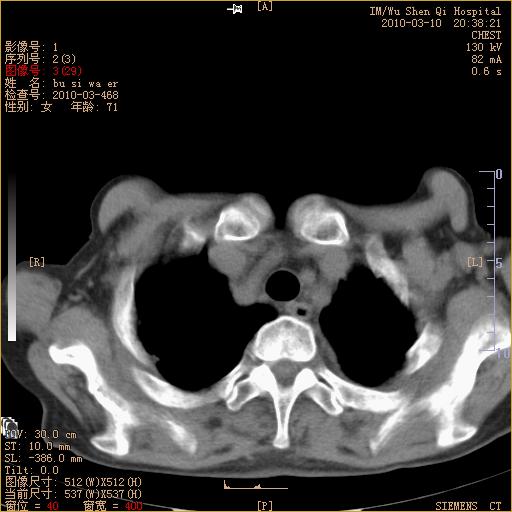

以下是引用随光逐影在2010-3-11 0:41:00的发言:[br]1)考虑左肺及右肺上叶继发性肺结核并左肺炎症感染。2)左侧支气管内膜结核可能;建议必要时行纤支镜检查。3)肺气肿。4)心包膜增厚(或少量心包积液)。5)左侧胸腔积液。